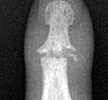

Early findings include soft tissue swelling and effusions. With progression of the infectious process, destruction of articular cartilage and bone can lead to radiographic findings of poorly defined articular erosions and joint space narrowing. Juxtaarticular osteoporosis and central erosions can also be noted and ankylosis of the joint may eventually result in the most severe cases.